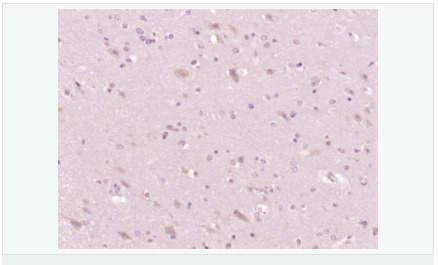

交叉反應(yīng):Human,Mouse,Rat(predicted:Pig,Cow,Horse,Rabbit) 推薦應(yīng)用:WB,IHC-P,IHC-F,ICC,IF,ELISA

| 產(chǎn)品應(yīng)用 | WB=1:500-2000 ELISA=1:5000-10000 IHC-P=1:100-500 IHC-F=1:100-500 ICC=1:100 IF=1:100-500 (石蠟切片需做抗原修復) not yet tested in other applications. optimal dilutions/concentrations should be determined by the end user. |